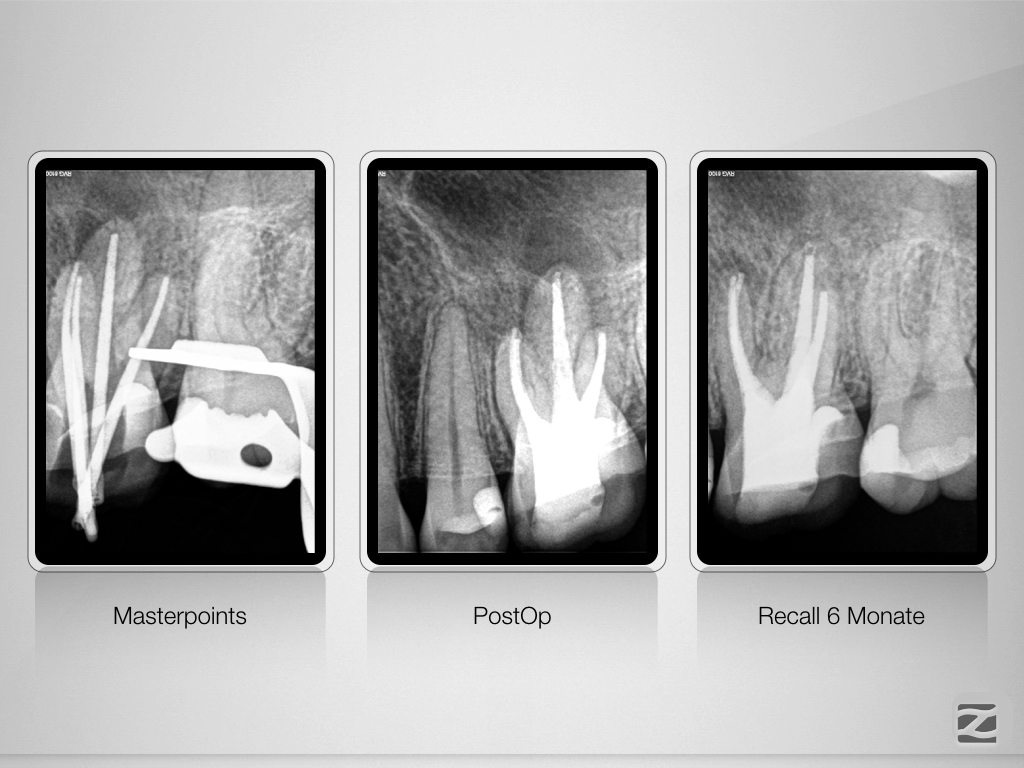

26D.011 Veröffentlicht 12. Februar 2021 am 1024 × 768 in Tiefe Aufgabelung, zwei Fisteln und ein Recall